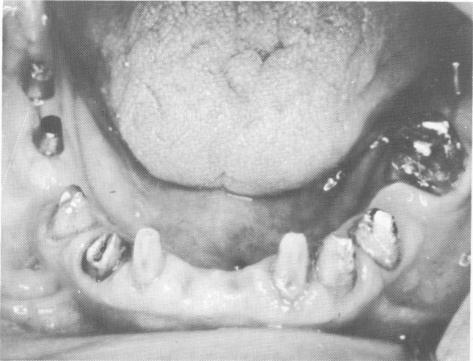

Fig. 15-34. Blade implants were implanted on both sides of the maxillary arch.

3 Blade implants are implanted on both sides of the maxillary arch